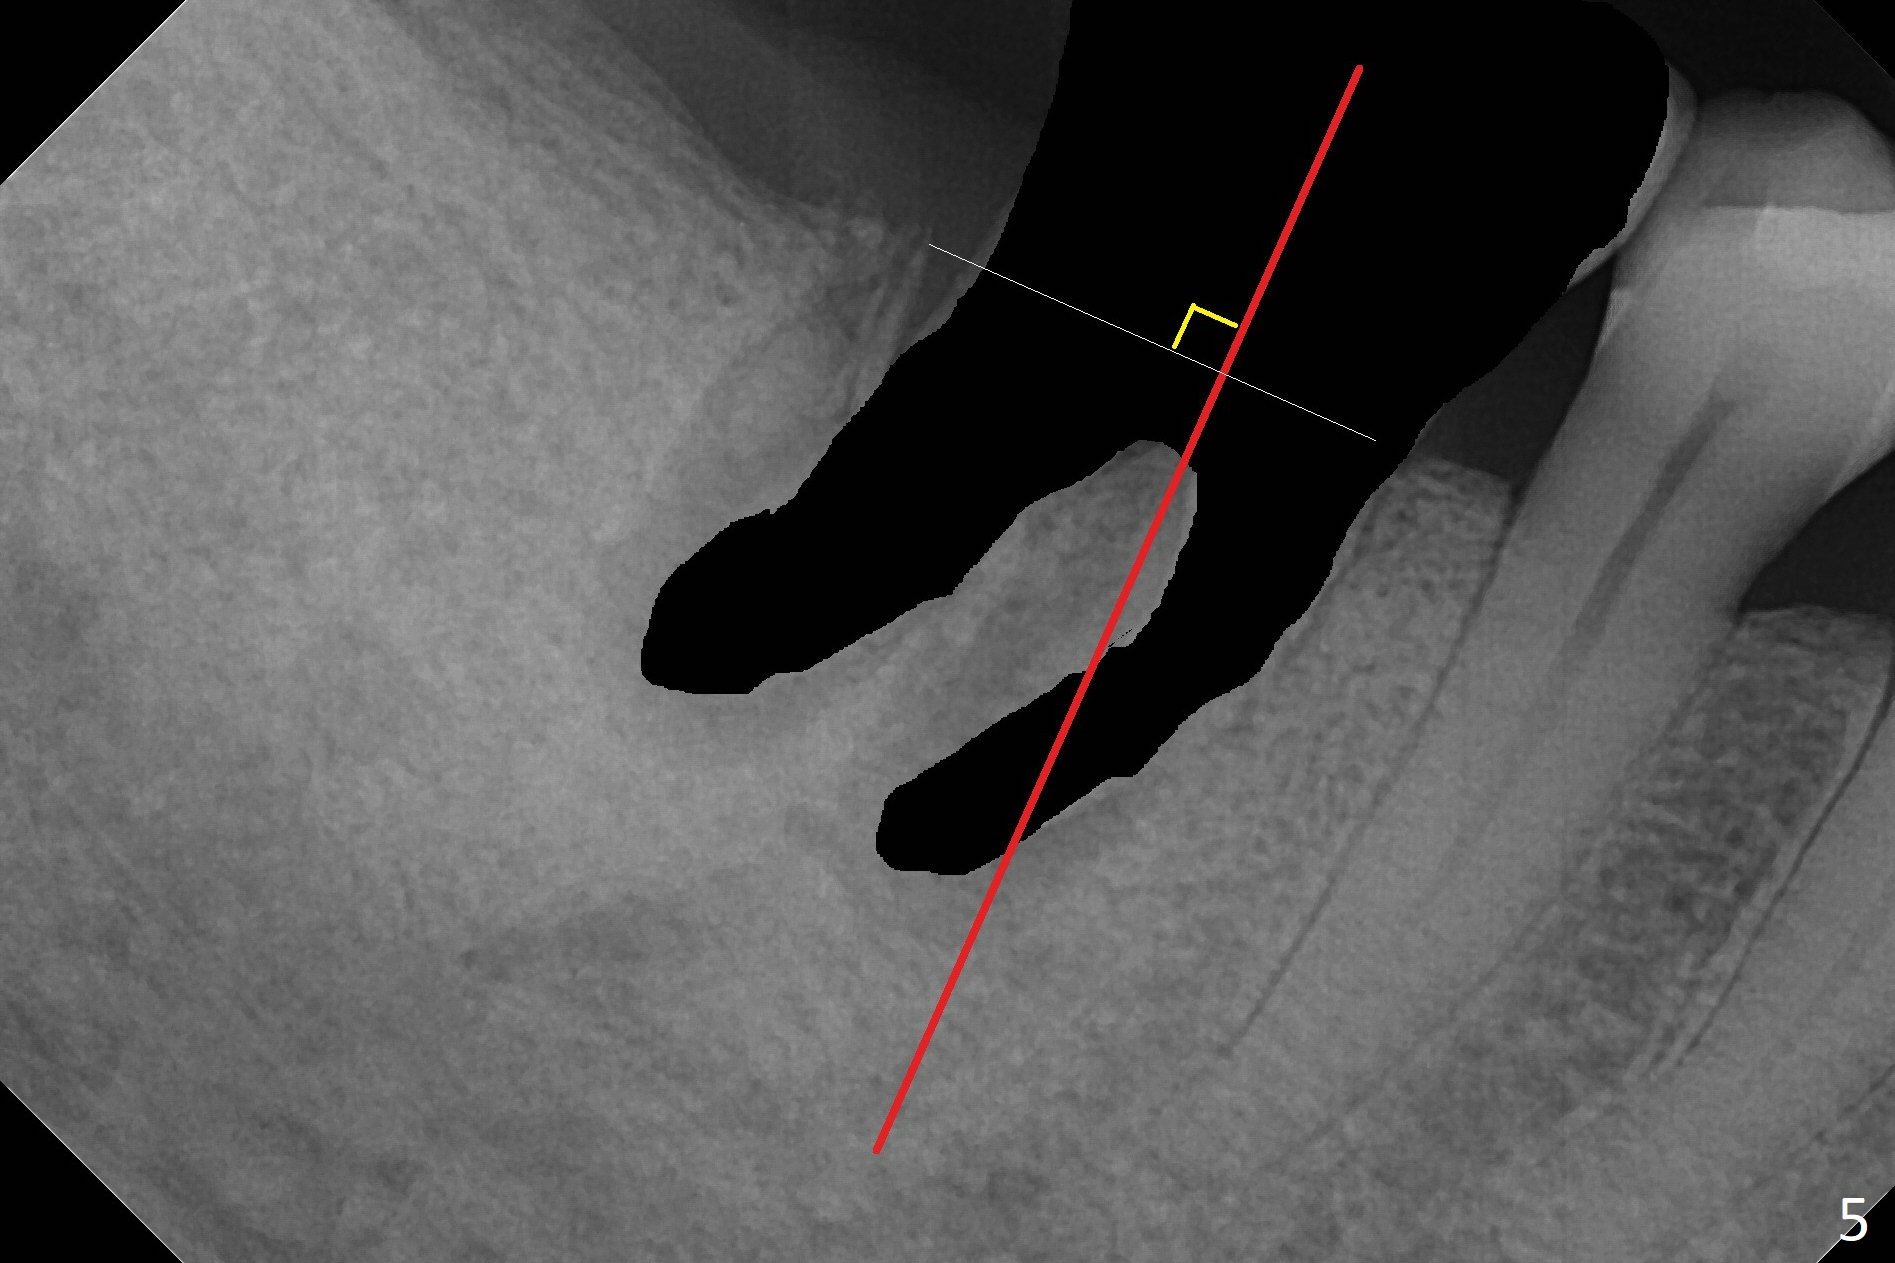

A 71-year-old woman (bruxer) wants to remove the tooth #30 (occlusal trauma, possible root fracture) for implant following the one at #14 (Fig.1). IBS abutment screw tends to loosen in functioning if the implant is placed too deep and/or off the longitudinal axis. If these two conditions are not controlled well, switch to a large tissue-level implant. A drawback of placing the implant in the septum is that the mesial margin of the abutment (Fig.2 pink) is subcrestal. If the implant is placed in the mesial socket (Fig.5 red line), the imagined abutment margin plane (white line) is parallel to the mesiodistal crests. Initial osteotomy entry point in the mesial socket and trajectory should be adjusted intraop (compare Fig.6 and 7) so that the apex of the implant will not be too close to the apex of the tooth #29 (to avoid truncating the neurovascular supply to the tooth (Fig.6 red arrowheads)) at the same time the abutment inclination is not too compromised (Fig.7). To prevent pressure upon the buccal (Fig.4 B) plate, osteotomy should be slightly lingual and/or the diameter of the implant is to be < 7 mm. Use a 3 mm unipost for provisional and probably 5 mm one for definitive restoration. Apply bonding to the post if the implant is 6 mm or less. The provisional margin should be wide and deep for deep margin and easy impression later. Use IS drills with 4 mm stopper for osteotomy if the septum is absent. Prepare Rongeur and surgical handpiece to remove the remaining septum if needed. Be wary of the distally curved root tip of #29. In fact there is a mesiodistal crack line (Fig.8 arrowheads) with buccal recession (Fig.9, 2 weeks preop).